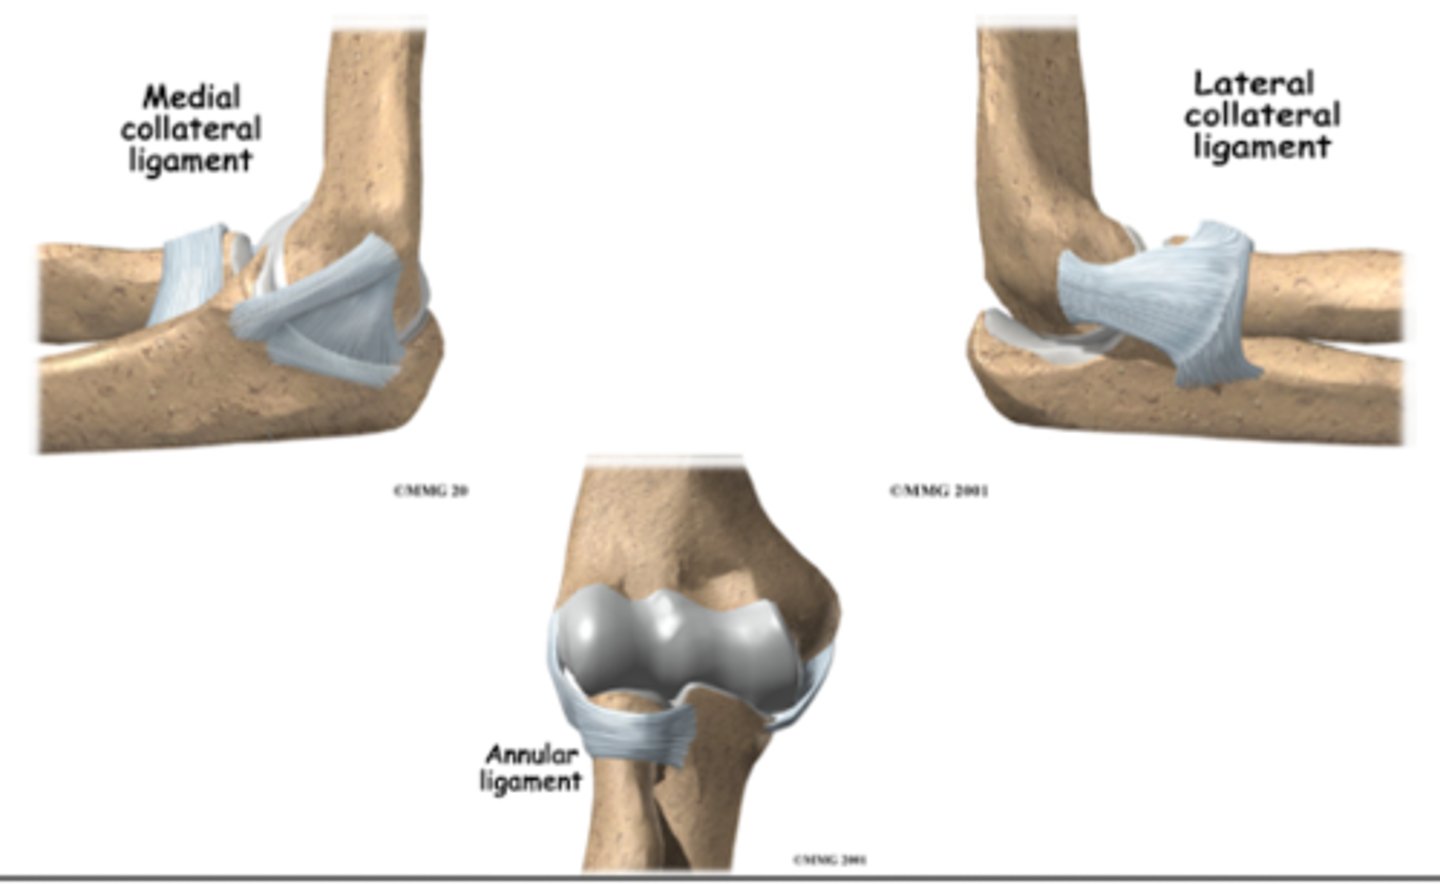

What THREE ligaments are involved in the elbow joint?

Medial collateral ligament

Lateral collateral ligament

Annular ligament